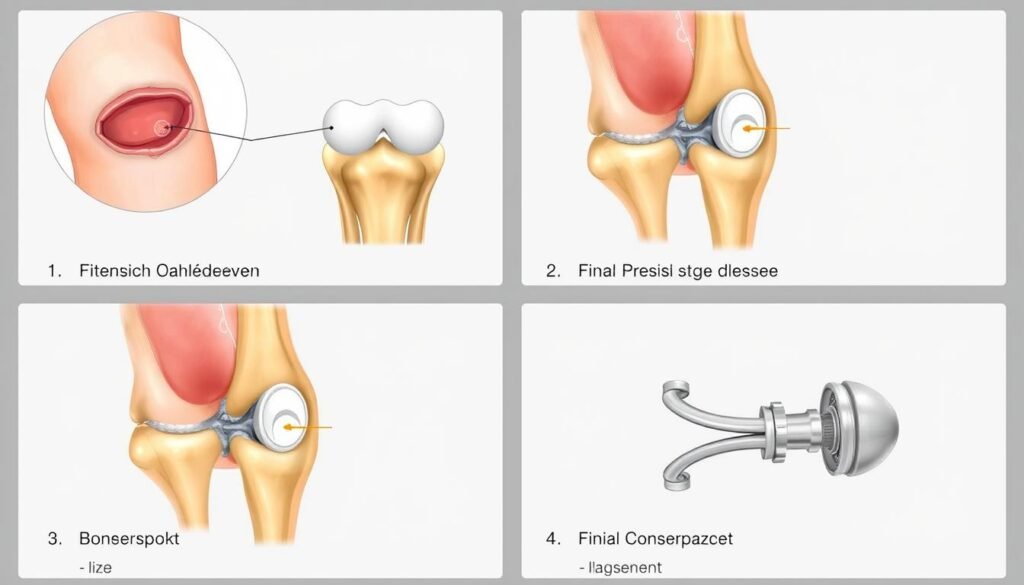

Ablauf der Operation einer Kniegelenksprothese

Die vier Hauptphasen der Knieprothesenimplantation

Die Implantation einer Kniegelenksprothese ist ein standardisierter Eingriff, der in der Regel 60 bis 90 Minuten dauert. Die Operation kann entweder in Vollnarkose oder mit einer Spinalanästhesie (Kreuzstich) durchgeführt werden. Der Patient befindet sich während des Eingriffs in Rückenlage.

Operationsschritte

- Hautschnitt: Der Operateur öffnet das Kniegelenk mit einem etwa 15-20 cm langen Hautschnitt an der Vorderseite des Knies.

- Präparation des Knochens: Die abgenutzten Knorpelflächen und ein dünner Knochenschnitt werden entfernt, um Platz für die Prothesenkomponenten zu schaffen.

- Anpassung der Prothese: Die Größe und Position der Prothesenkomponenten werden genau bestimmt und angepasst.

- Probeimplantation: Vor der endgültigen Fixierung werden Probekomponenten eingesetzt, um die Passform und Beweglichkeit zu überprüfen.

- Fixierung der Prothese: Die endgültigen Prothesenkomponenten werden entweder mit Knochenzement befestigt oder bei zementfreien Modellen durch Press-fit-Technik verankert.

- Wundverschluss: Nach Einlage einer Drainage werden die Weichteile und die Haut wieder verschlossen.